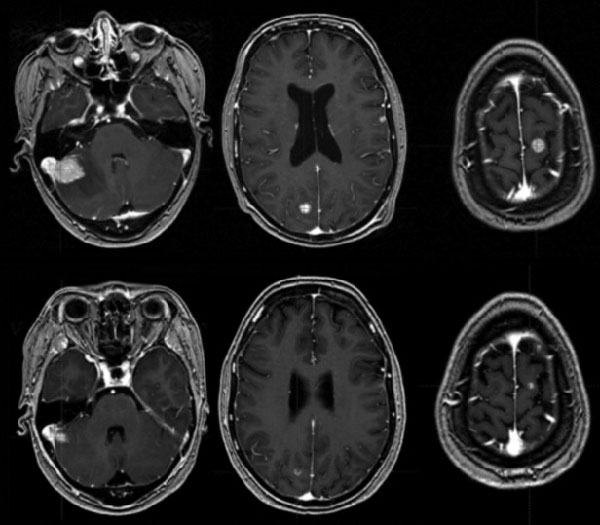

单纯SRS治疗发生脑转移SCLC效果更佳

美国科罗拉多大学Robin等报告的研究表明,有些小细胞肺癌患者可以接受单纯立体定向放射外科(SRS),这项迄今最大样本SRS治疗SCLC数据分析显示,单纯SRS有总生存优势,(Lung Cancer. 2018, 120: 88-90)

全脑放疗(WBRT)是脑转移SCLC患者标准治疗,但WBRT有明确的认知功能毒性,局灶性脑转移可选择单纯SRS,不过SCLC中这种治疗研究数据较少。研究者分析了美国国家癌症数据库(NCDB)中诊断时有脑转移,多元Cox回归和倾向评分匹配(PSM)分析SRS与WBRT±SRS策略对总生存的影响。

共纳入5952例患者中位随访40.0个月,WBRT治疗者5752例,SRS治疗者200例。SRS治疗者OS长于WBRT±SRS患者,中位OS分别为10.8个月和7.1个月(HR=0.65, 95%CI 0.55~0.75,P<0.001),校正了合并症、颅外转移、年龄、种族/民族和性别等变量的多因素分析中OS优势保持(HR=0.70,95%CI 0.60~0.811,P<0.001),PSM分析中也得到证实。亚组分析显示,SRS治疗对比SRS联合WBRT治疗的OS无显著差异(P=0.601)。

研究者认为,该研究为现阶段单独SRS治疗SCLC患者的最大样本数据分析,SRS治疗者OS更长,提示SRS可能适用于一些SCLC患者。有必要对SRS在SCLC中的应用进行前瞻性研究。